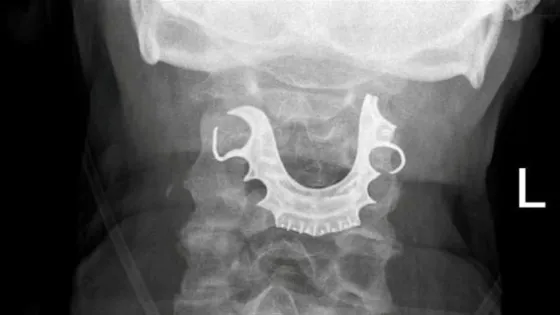

وطنا اليوم:في حادثة إنسانية لافتة، كادت أن تنتهي بمأساة، نجح ضابط الإسعاف العامل في غرفة العمليات والسيطرة (911) في إنقاذ سيدة تعرضت لاختناق حاد بعد ابتلاع أسنان صناعية، وذلك من خلال تقديم إرشادات دقيقة عن بُعد.

وفي التفاصيل، قام الضابط بتوجيه المتواجدين مع المصابة خطوة بخطوة لتنفيذ إجراءات الإسعافات الأولية اللازمة، بما في ذلك فتح مجرى التنفس والتعامل السريع مع الحالة، الأمر الذي أسهم في استقرار وضعها الصحي واستعادة وظائفها الحيوية قبل وصول فرق الإسعاف إلى الموقع.

وعند وصول الكوادر المختصة، تم نقل السيدة إلى المستشفى لاستكمال الرعاية الطبية اللازمة، وسط إشادة بسرعة الاستجابة وكفاءة التعامل مع البلاغ.